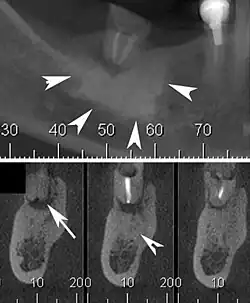

| Cone beam CT scan presenting a diffuse hyperdense lesion in the apex of a mandibular molar (arrowhead, top) adjacent to an inflammatory periapical lesion (arrow, bottom).[1] | |

Diagnosis typically involves a clinical examination by a dentist or endodontist, complemented by imaging studies such as cone-beam computed tomography. Radiographically, condensing osteitis presents as a localized radiopaque lesion at the root apex of the affected tooth.[5]